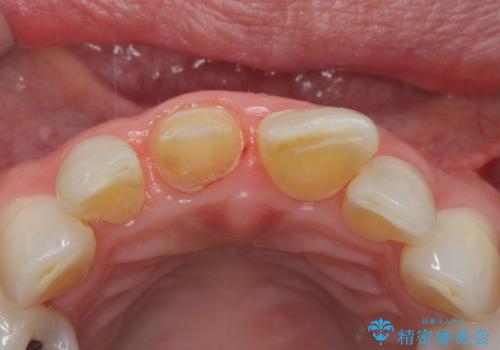

検査の結果、歯は大きく折れておらず、骨の中に埋め込まれていた状態であったため、部分矯正で歯を引っ張り出していきます。

- 右上1/部分矯正:110,000円 根管治療:保険 仮歯:11,000円 ジルコニアクラウン(スペシャル):143,000円費用は治療当時の料金となります

ぶつけて埋まってしまった歯は、場合によって矯正治療で引っ張り出すことで保存することができます。

今回は歯の神経が死んでしまっていたため、根管治療後に被せ物を装着して見た目の綺麗さを回復しました。